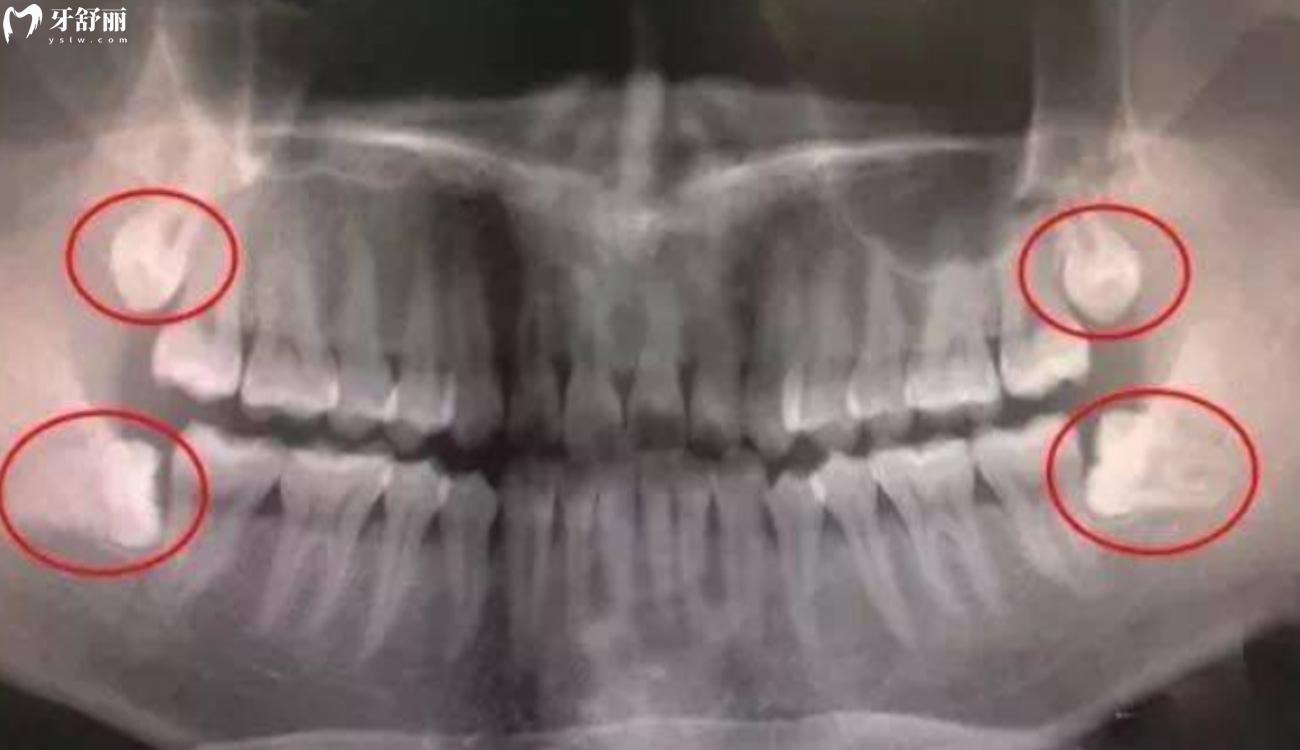

智齿也叫第三磨牙,长在磨牙后区,也就是第二磨牙的远端。智齿分别会长在上下左右各一颗,分布在四个角。

具体智齿的数量和位置,每个人的情况都会不同,因人而异。有的阻生、横向甚至倒置,智齿的变异成都相当大。